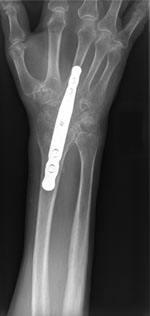

(Left) The three wrist bones that are removed in a proximal row carpectomy, are shaded here. (Right) An x-ray image of a wrist after a proximal row carpectomy.

In a fusion, the bones of the wrist are held together with a combination of a plate, screws, and pins.